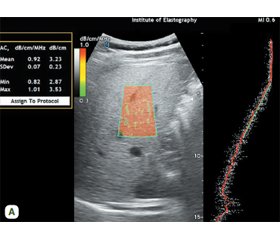

- Динник О.Б., Марунчин Н.А., Ковалеренко Л.С., Закревська С.О., Орієвська І.І., Жайворонок М.М. Роль одночасної ультразвукової еластометрії та стеатометрії при хронічних дифузних захворюваннях печінки інфекційної та неінфекційної етіології. Актуальна інфектологія. 2019. Т. 7. № 2. С. 46-47.

- Kobyliak N, Dynnyk O, Savytska M, Solodovnyk O, Zakomornyi O, Оmеlchenko O, Kushnir A, Titorenko R. Accuracy of atte–nuation coefficient measurement (ACM) for real-time ultrasound hepatic steatometry: Comparison of simulator/phantom data with magnetic resonance imaging proton density fat fraction (MRI-PDFF). Heliyon. 2023 Oct 4;9(10):e20642. doi: 10.1016/j.heliyon.2023.e20642. PMID: 37818006; PMCID: PMC10560839.

- Zhaivoronok ММ, Fedusenko ОА. Correlation between the hepatorenal index and ultrasound attenuation coefficient for evalua–tion of hepatic steatosis. Radiation diagnostics, radiation therapy. 2024;15(1):35-42. https://doi.org/10.37336/2707-0700-2024-1-4.